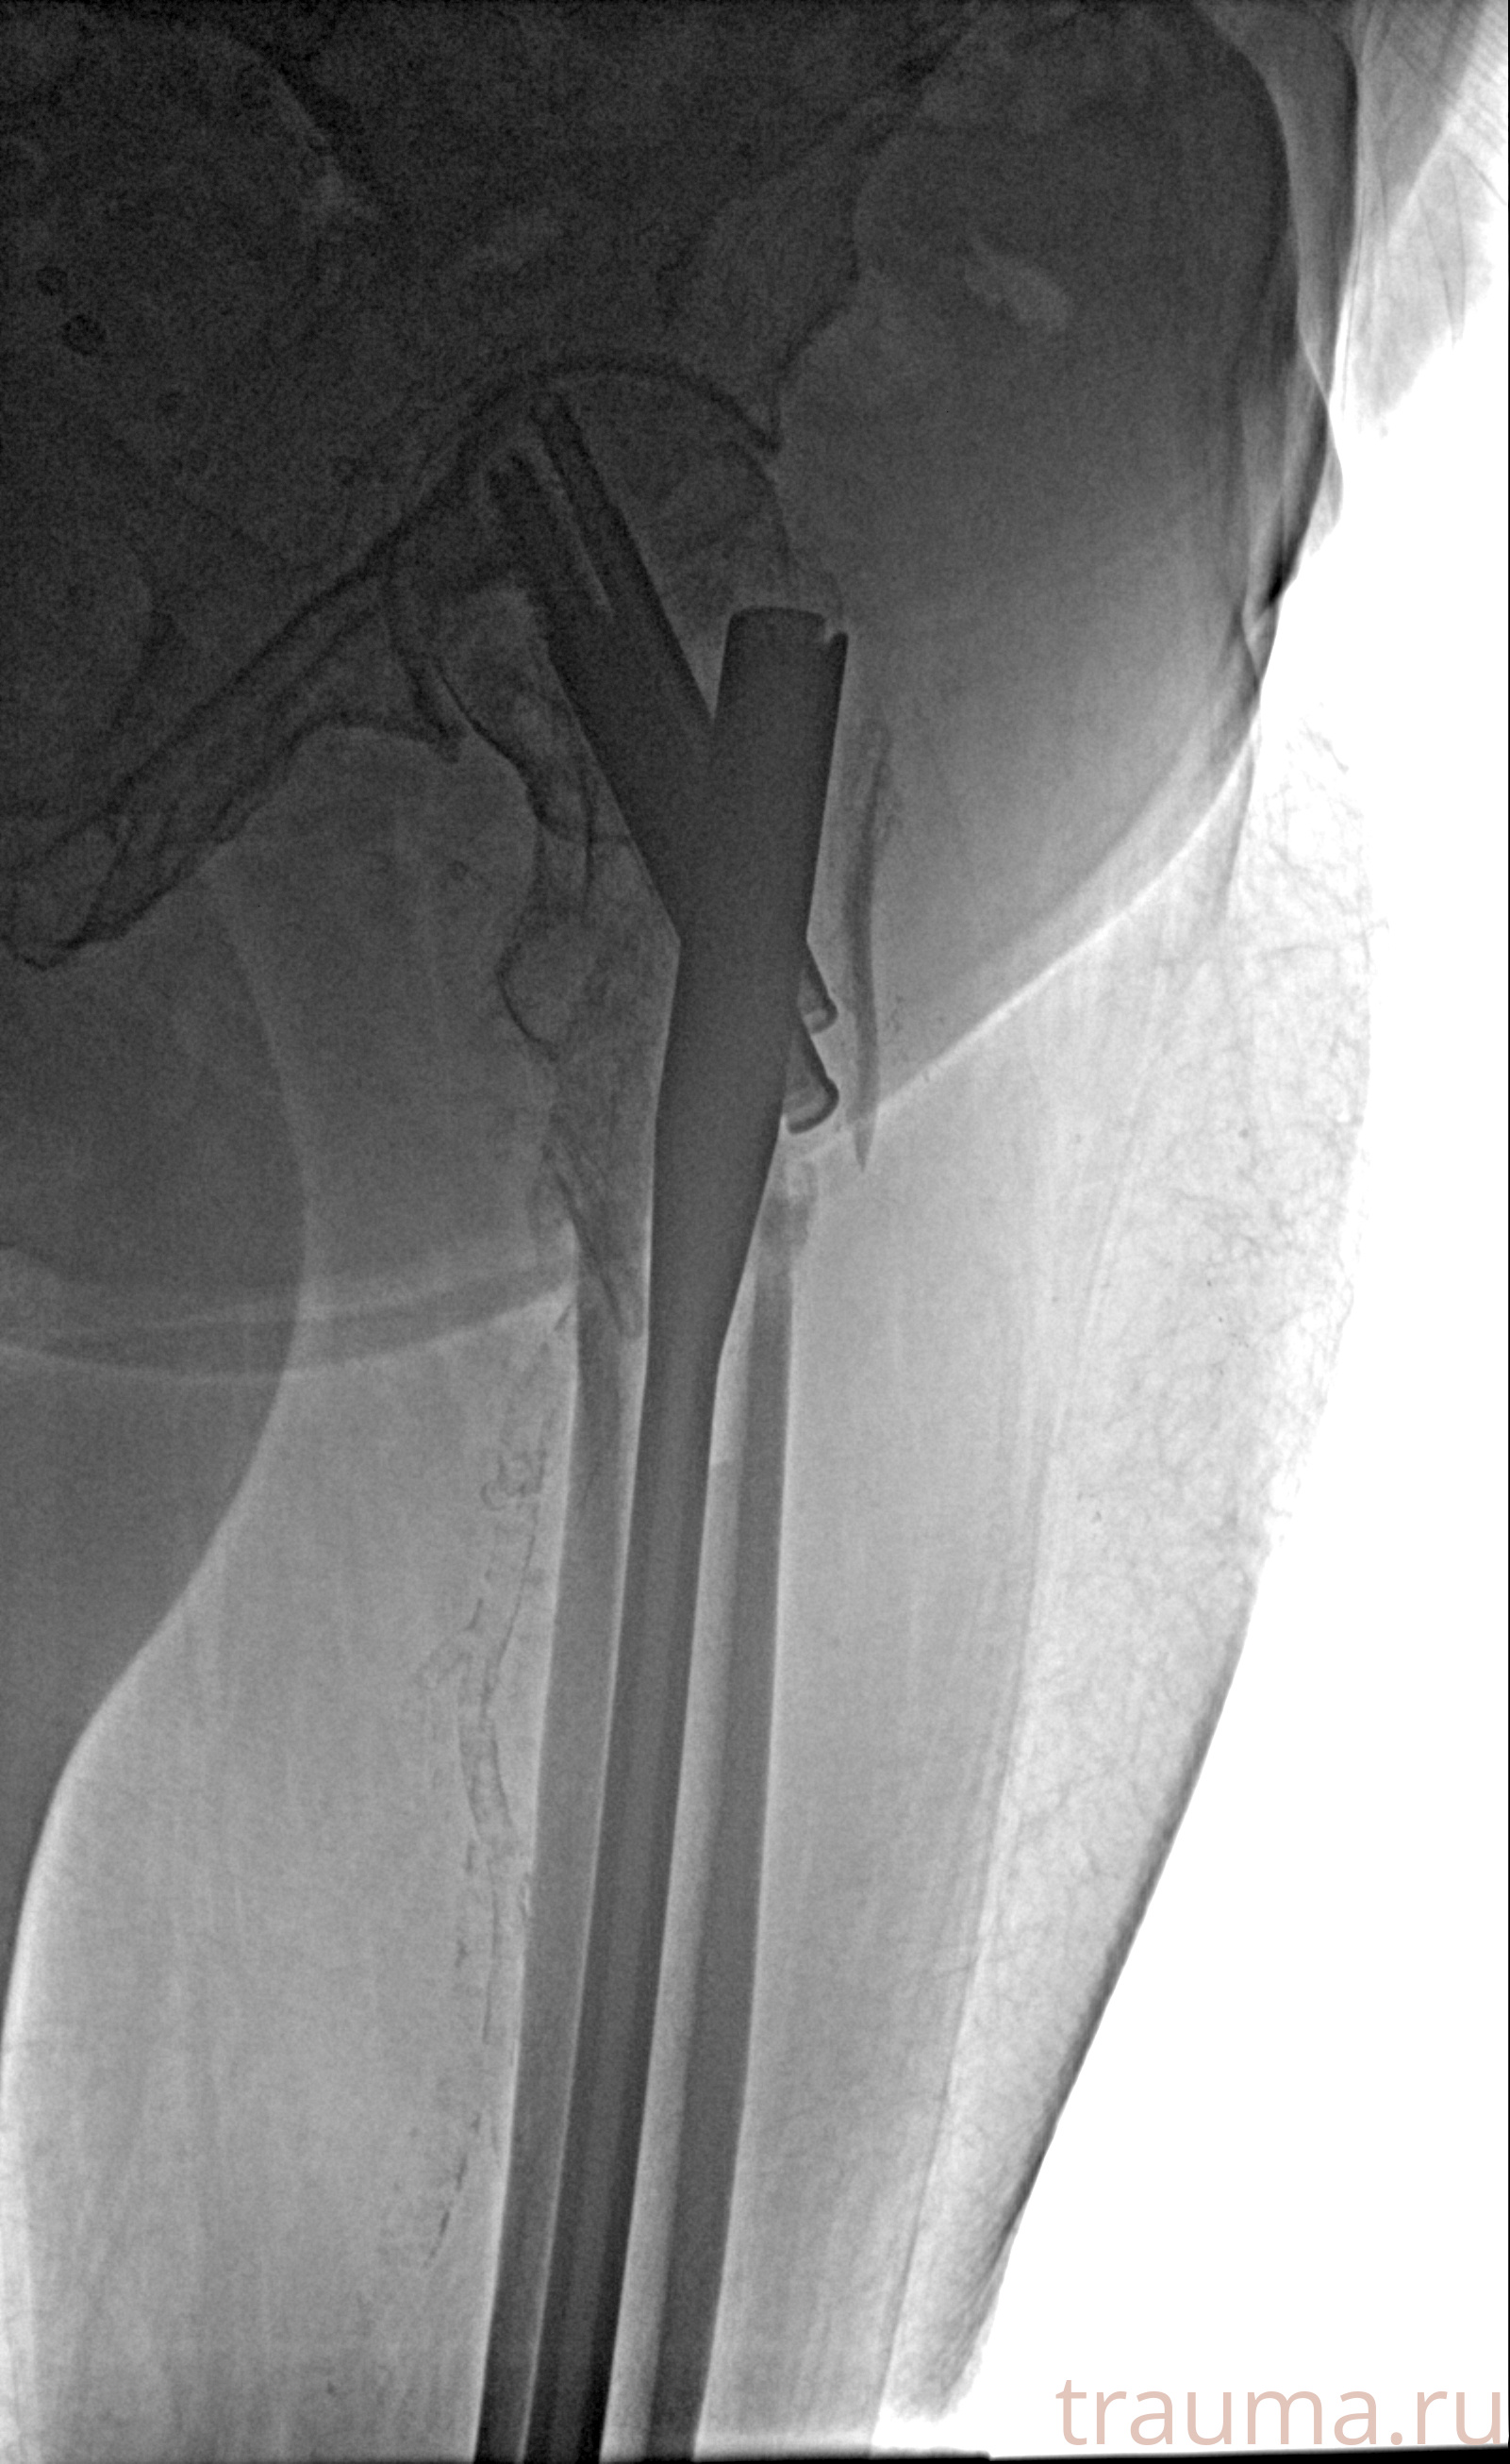

Рентгенограммы

24.01.2026

Рентген на дому: по вашему адресу приезжает врач-рентгенолог, травматолог-ортопед с мобильным рентгеновским аппаратом, проводит диагностику травмы или заболевания, делает необходимые рентгенограммы, дает рекомендации по дальнейшему лечению. Получить качественные снимки в домашних условиях возможно благодаря уникальной методике, разработанной МосРентген Центром для института  Склифосовского